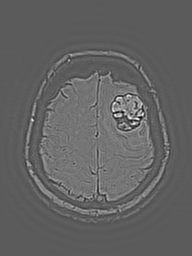

eigenMRI Filtered

MRI view

Local Lesion Window · Lesion Origin (Tracked)

Local lesion window

Lesion Origin anchor for longitudinal tracking

ABER anatomic boundary emphasis region

Overlay margin / curvature / global